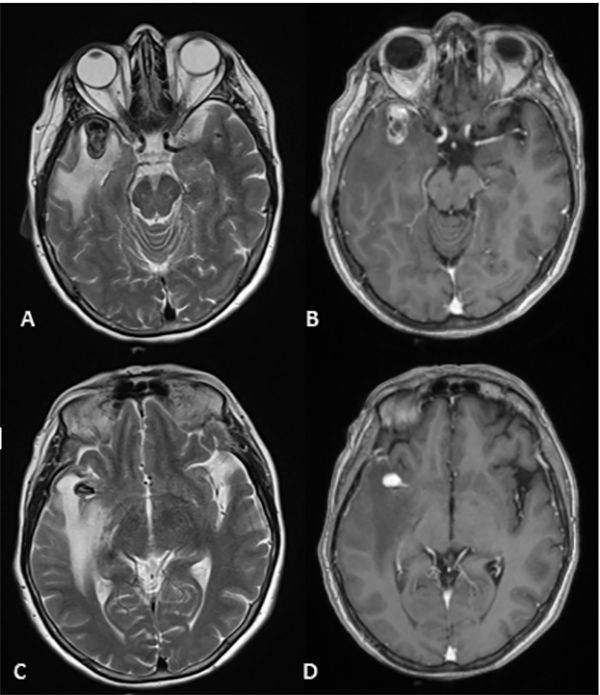

El laboratorio se encontraba dentro de parámetros normales, se realizó resonancia magnética (RM) de cerebro sin contraste, la cual mostró una imagen hipointensa en secuencia GRE a nivel del surco silviano derecho y adyacente a la misma se observa edema perilesional que se extiende al lóbulo temporal (Figura 1). Se realizó angiotomografìa para descartar una malformación vascular subyacente, en la cual se advirtió una dilatación aneurismática polilobulada de 20 x 6 x 9 milímetros (Figura 2).

Figura 2: Se observa en Angiotomografía de vasos intracraneanos en sus tres cortes anatómicos a nivel de la bifurcación de la arteria cerebral media derecha una dilatación aneurismática sacular, irregular y polilobulada sin evidencia de signos de trombosis o aterosclerosis.

Figura 3: (RMN) Se observa en corte axial lesión expansiva marcadamente hipointensa en T2 localizada a nivel temporal anterior derecho en relación con el sector distal de la arteria cerebral media homóloga. Tras la inyección de contraste presentó refuerzo heterogéneo, con un componente de aspecto trombosado en el sector basal de la misma, asociado a extenso edema periférico (A, B, C y D).